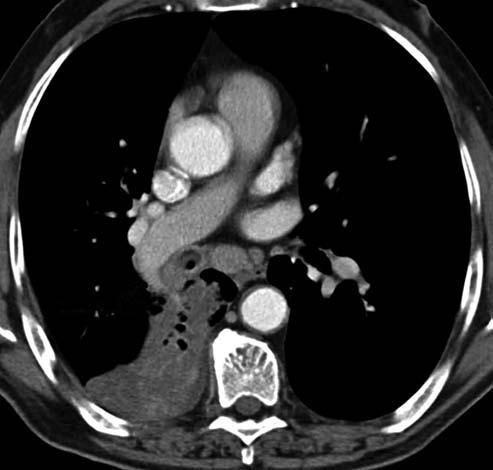

The initial physical examination showed the following: heart rate, 100 beats per minute; blood pressure, 108/65 mm Hg; oxygen saturation, 94% on room air (measured by pulse oximetry); and normal temperature. Chest auscultation revealed diminished breath sounds over the right hemithorax and bilateral expiratory wheeze. The patient's chest radiograph showed a right lower lobe infiltrate. A CT scan of the chest showed a right sided endobronchial mass and right lower lobe atelectasis (Figure 1). The patient was treated with intravenous piperacillin/tazobactam and inhaled bronchodilators.

Figure 1 – CT scan of the lungs shows an endobronchial mass (arrow) on the right side with right lower lobe atelectasis.